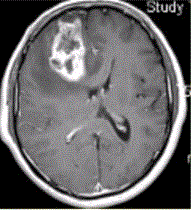

患者女,67岁,头痛伴呕吐1周。既往体健。MR表现如下图。临床拟诊为A.脑脓肿B.转移瘤C.成胶质胞瘤D.少枝胶质细胞瘤E.成髓细胞瘤

问题 患者女,67岁,头痛伴呕吐1周。既往体健。MR表现如下图。 临床拟诊为

选项 A.脑脓肿 B.转移瘤 C.成胶质胞瘤 D.少枝胶质细胞瘤 E.成髓细胞瘤

答案 C